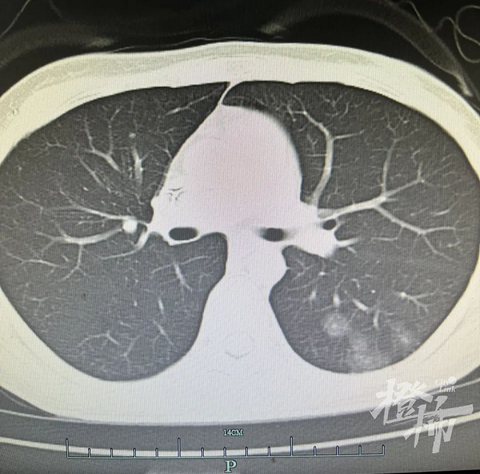

北青网 原标题:10年5次患癌,这个24岁单腿姑娘瘦弱的身影令人心疼!体重66斤的她,已数不清是第几次住进病房…… 在许许多多的癌症患者中,有一类患者似乎特别不幸,不久前才接受过治疗的癌症,又在身体里“卷土重来”。多数市民也许都会觉得是第一次所患的癌症复发或者转移了。但对于这一类患者,他们终其一生都要时刻警惕癌症侵袭。 体检发现两肺多发小结节可能“癌”又来了! “王主任,体检报告说我肺里有多发性结